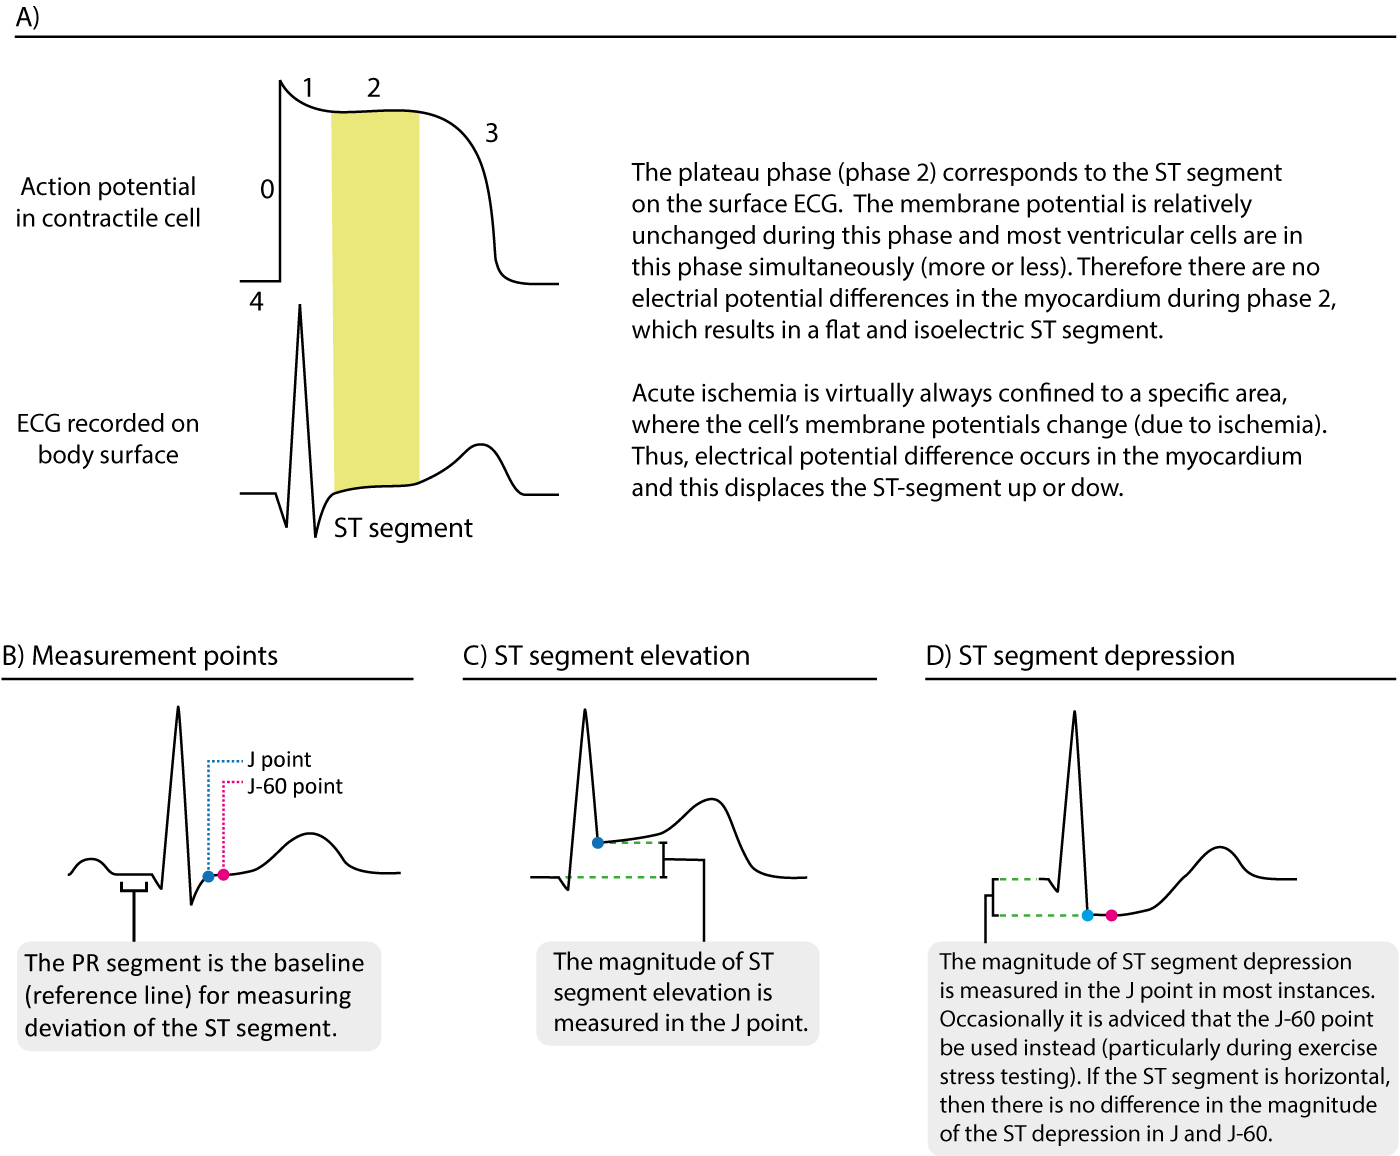

ECG Ischemic Heart Disease 1 7 Introduction YouTube